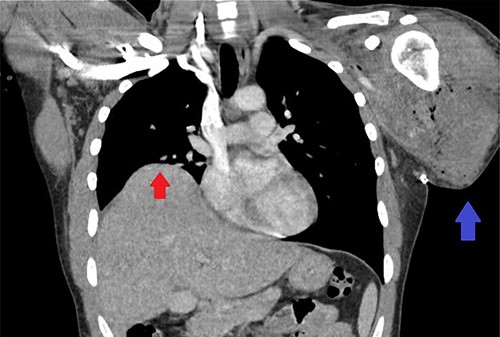

We present a case of a 25-year-old male who sustained a traumatic left-sided transhumeral amputation in a single car roll-over motor vehicle collision (MVC). The patient was transferred to a tertiary care center under the care of the plastic surgery service for further management and plans for operative reinnervation of his left upper extremity (LUE). Upon arrival, the patient’s only complaint was discomfort to the LUE stump. He was subsequently pan-scanned with a computed tomography (CT) due to the mechanism of the crash sustaining significant blunt abdominal trauma. The patient was found to have elevation of his right hemidiaphragm, concerning for possible diaphragmatic injury demonstrated in Fig. 1. A fluoroscopic sniff test was completed showing no inferior or superior excursion of the right diaphragm during inspiration or expiration with paradoxical chest wall motion providing diagnostic evidence of right hemi-diaphragmatic paralysis.

CT scan of the chest showing right-sided elevation/eventration of the diaphragm concerning for phrenic nerve injury (Red arrow); post-operative changes to LUE stump (Blue arrow).